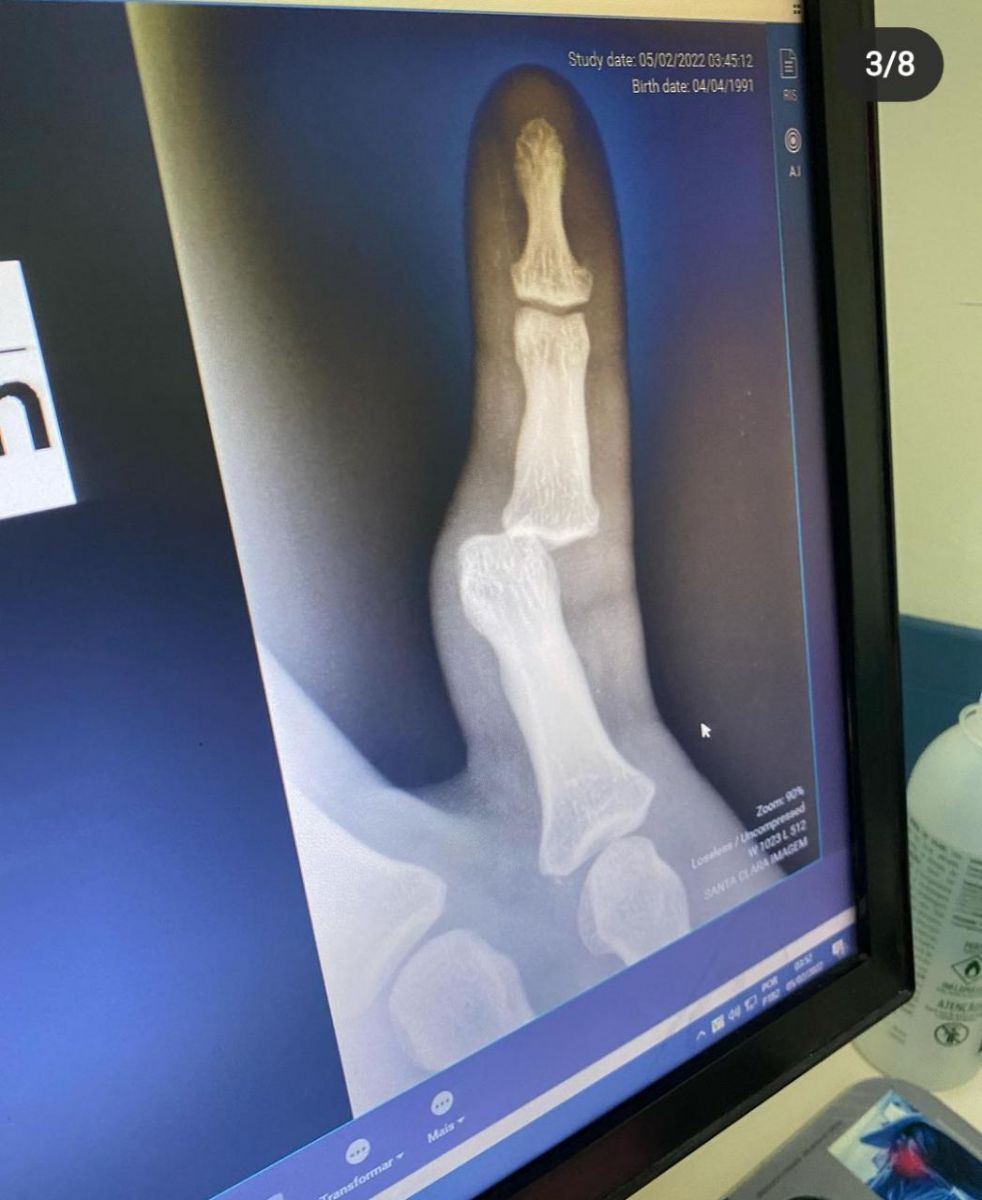

"Gente, bebi demais ontem, levei um tombo ali perto da escada, cai em cima do dedo, quebrei o dedo e cai de cara, é bem isso", contou.

Lucas disse em um vídeo em tom de humor ao lado da família, que realizou uma tomografia e precisou de medicamentos, e fez referência a sua nova música, “Amava Nada”, lançada ontem (5) em parceria com Marília Mendonça. “Queria fazer juz ao nome do DVD, rolê diferenciado”, relatou em tom de brincadeira.